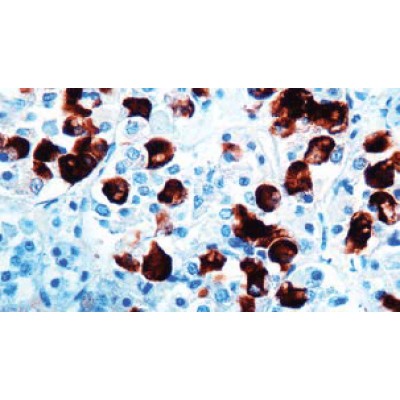

Immunogen: Synthetic human ACTH 1-24.

Positive Control: Pituitary

Cellular Localization: Cytoplasmic

Specificity: This antibody reacts with human ACTH. This antibody cross-reacts with

ACTH in a wide variety of mammalian species. Traces of contaminating antibodies have

been removed by solid phase adsorption.